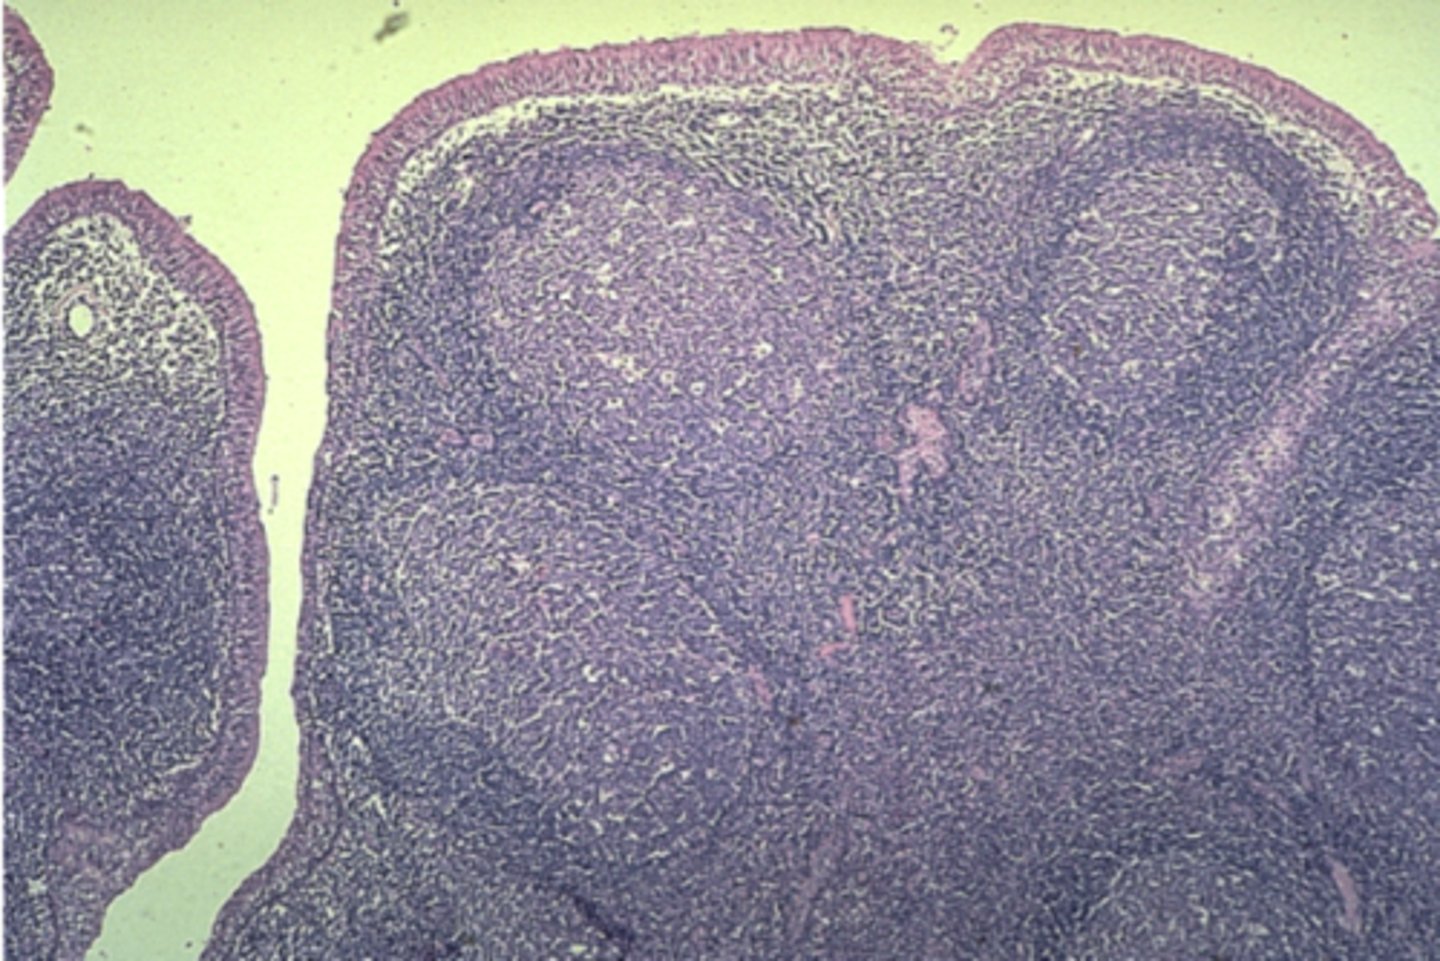

Lymph node

What is this?

Appendix

What is this?

Tonsil

What is this?